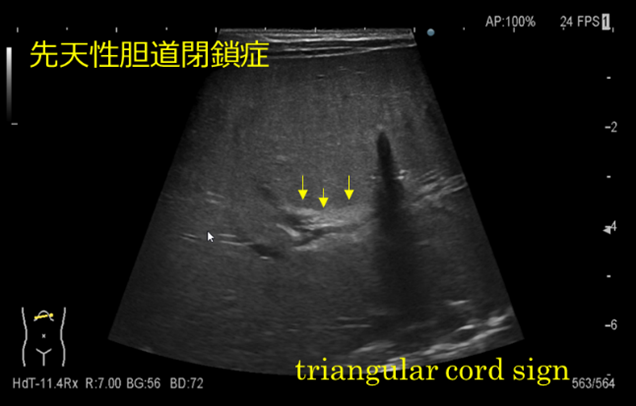

先天性胆道閉鎖症とは

一度形成された肝外胆管が何らかの炎症で閉塞する状態のことです。

新生児期あるいは乳児期早期に胆汁うっ滞・閉塞性黄疸症状で発症します。